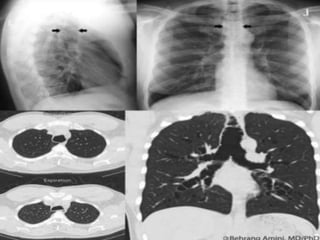

 Signs on CXR include the identification of

parallel linear densities, tram-track opacities, or

ring shadows reflecting thickened and

abnormally dilated bronchial walls. These

bronchial abnormalities form a spectrum from

subtle or barely perceptible 5-mm ring

shadows to obvious cysts. Tubular branching

opacities conforming to the expected bronchial

branching pattern may result from fluid or

mucous filling of bronchi

Tram Line in LUL and signet ring in RUL